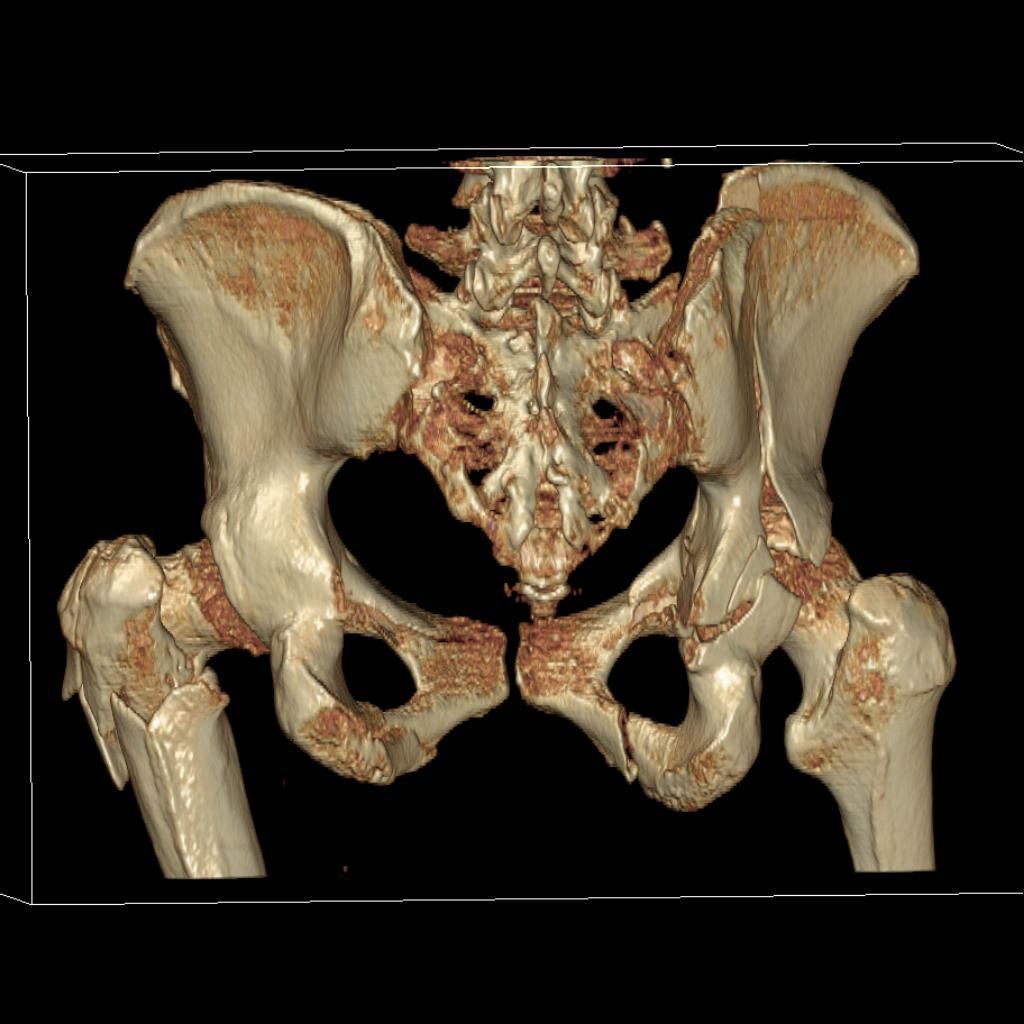

В чем основные различия между КТ и МРТ? Магнитно-резонансная томография позволяет выявить повреждения суставной капсулы, связок и мягких тканей. На компьютерных томограммах хорошо визуализируются мелкие костные дефекты, которые не видны на рентгене.

В ортопедии и травматологии рентгенологическое исследование используют для диагностики деформирующего коксартроза, артритов, асептического некроза головки бедренной кости, костных новообразований, вывихов, переломов шейки бедра и т. д. Рентгтенография позволяет подтвердить наличие патологии, но не всегда дает достаточно информации. Нельзя, например, получить послойное изображение тканей, из-за чего врачи не могут определить точную локализацию патологических изменений.